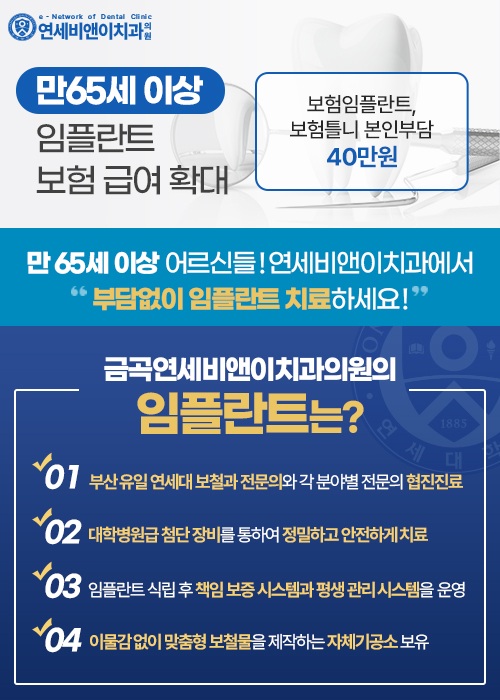

연세대학교 치과 병원의 시스템을 그대로 도입하여

임플란트 클리닉을 운영합니다.

연세대 출신의 대표원장과 분야별 전문의 원장들의

꼼꼼한 진료와 협진 진료 시스템으로 운영합니다.

자체기공소를 운영하여 당일 보철 수정이 가능하고

외부 기공소보다 더 정밀한 맞춤 제작이 가능합니다.

치료가 완료되어도 정기 구강검진과

시기를 꼼꼼히 체크하여 주치의 개념의 평생관리 시스템을 운영합니다.

오스템임플란트, 네오임플란트, 디오임플란트